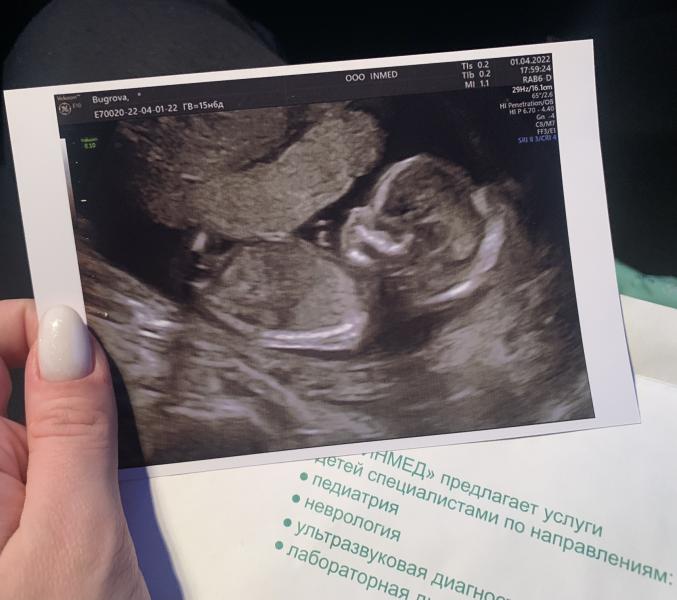

Ходили сегодня на узи,узнать пол в конвертик )На следующей неделе будем делать гендер пати 😍Какой малыш уже большой !Даже не верится !Узистка конечно шикарная .Всё-всё как на скрининге ,все органы замерила,всё рассмотрела,всё показала .Только вот пол,как она так незаметно посмотрела !?)Я думала что я всё увижу ,ещё переживала ,что сюрприза не будет )Но в итоге ,я теперь в сомнениях,почему я не увидела пипирочку ?)Я почему-то была уверена,что мальчик ,а теперь закрались сомнения,может всё таки и ...